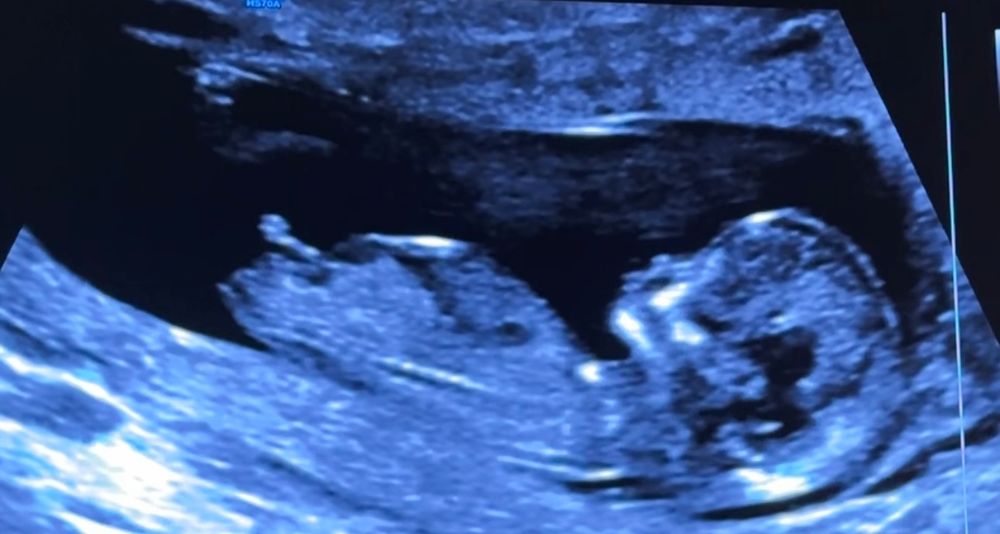

Пол по бугорку на 1 скрининге

Тоже думаю девочка 💖

Мне кажется, что это мальчуган 💙

Девочковый бугорок)